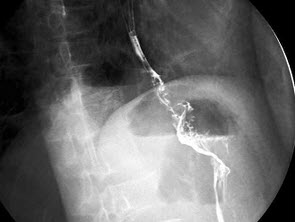

289、单项选择题

男,71岁,脾大、腹水、肝管结石2年,结合图像,最可能的诊断为()

A.正常表现

B.会厌征

C.食管多发憩室

D.食管溃疡

E.食管癌